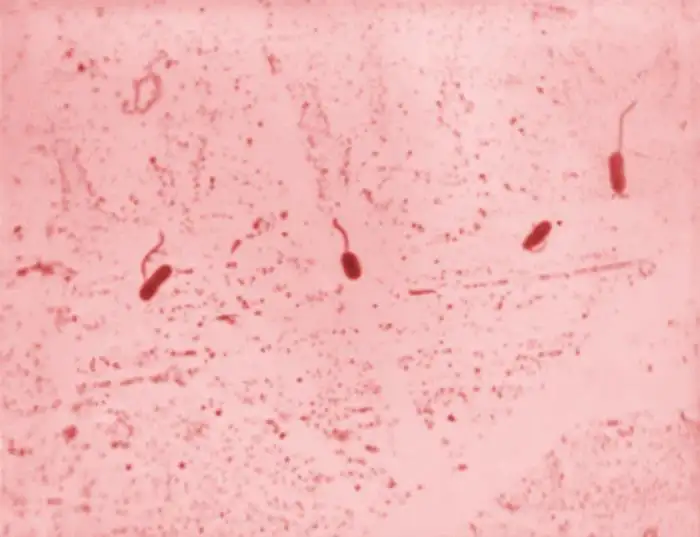

讽刺的是,就在斯诺在伦敦绘制他的死亡地图的同时,一位意大利显微学家菲利波·帕奇尼正在佛罗伦萨进行着另一项同样具有开创性却被完全忽视的工作。帕奇尼使用显微镜检查霍乱死亡者的肠道组织,发现了一种前所未见的微生物——一种微小的、逗号形状的细菌。他将这种生物命名为"弧菌",并在1854年发表了一系列论文,详细描述了这种细菌与霍乱之间的关系。然而,当时医学界的主流观点仍然顽固地坚持瘴气说,帕奇尼的发现被完全忽视了。他孤独地继续着自己的研究,直到1883年在贫困中死去。直到几十年后,科学界才承认了帕奇尼作为霍乱病原体发现者的地位。1966年,国际细菌学命名委员会正式将霍乱病原体命名为"霍乱弧菌帕奇尼",以纪念这位被遗忘的科学先驱。

1883年,德国细菌学家罗伯特·科赫前往埃及和印度调查霍乱疫情。在亚历山大港和加尔各答的实验室里,科赫独立地"重新发现"了帕奇尼二十多年前就已经描述过的逗号形细菌。科赫成功地在纯培养中分离出了这种细菌,并详细描述了它的形态特征。他在给德国政府的报告中写道:这是一种略微弯曲的杆菌,像逗号一样,它在肠道粘液中大量存在。科赫的发现很快得到了广泛认可,他因此获得了1905年的诺贝尔生理学或医学奖。而帕奇尼的贡献,则几乎被历史完全遗忘,直到二十世纪后期才被重新发现和承认。

霍乱弧菌是一种极其狡猾的病原体。它的外形像一根微小的逗号,通常只有1.5到2微米长,0.5微米宽。在显微镜下,它们看起来像一群活泼的小鱼,依靠一根长长的鞭毛在液体中高速游动。当这种细菌通过污染的水或食物进入人体后,它们会在胃酸的屏障下损失大部分,但少数幸存者会进入小肠,那里温暖、潮湿、富含营养的环境为它们提供了理想的繁殖场所。在抵达小肠后的几小时内,这些细菌会迅速增殖,每二十分钟就能翻一番。一个霍乱患者在腹泻高峰期,每毫升肠液中可能含有超过一亿个细菌。